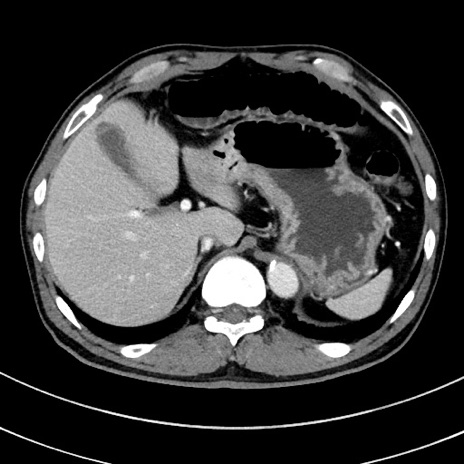

症例8(横断像)

【症例】 60歳代男性

【主訴】 黒色吐物

【現病歴】 4日前から嘔気自覚、2日前の朝食後にも嘔気あり、自分で手で嘔吐反射起こし嘔吐したところ血が混ざっていたため受診。

【既往歴】 5年前汎発性腹膜炎を伴う急性虫垂炎で手術、高血圧、前立腺肥大症、高脂血症

【身体所見】 腹部正中に手術癩痕あり 腹部平坦・軟圧痛なし膨満感あり

【データ】WBC 8400、CRP 4.54